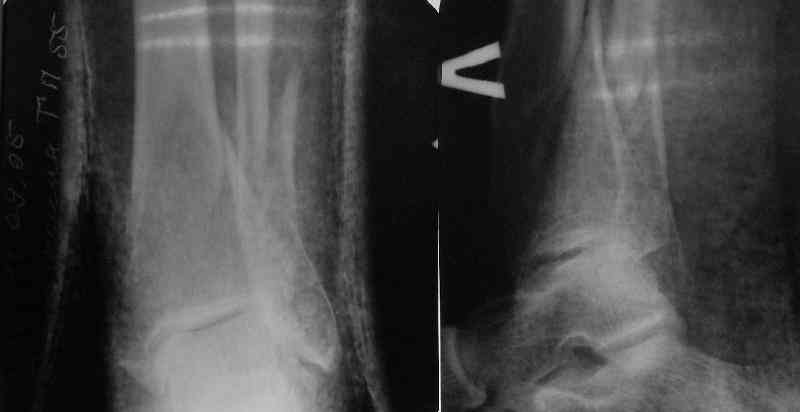

Проксимальный и дистальный переломы tibia

Направили к нам пациентку 35 лет с переломом дистального отдела костей голени.

У нас сделали снимок сзахватом обоих суставов - еще и проксимальный метафиз сломан. Чем бы у вас фиксировали такой перелом? Как его правильно закодировать по классификации АО?

41.A2.1 for a proximal fracture

42.B1.3 for a distal fracture

Is very difficult take an exactly AO/OTA group for a good classification Probably the locked IM nail is a good option.